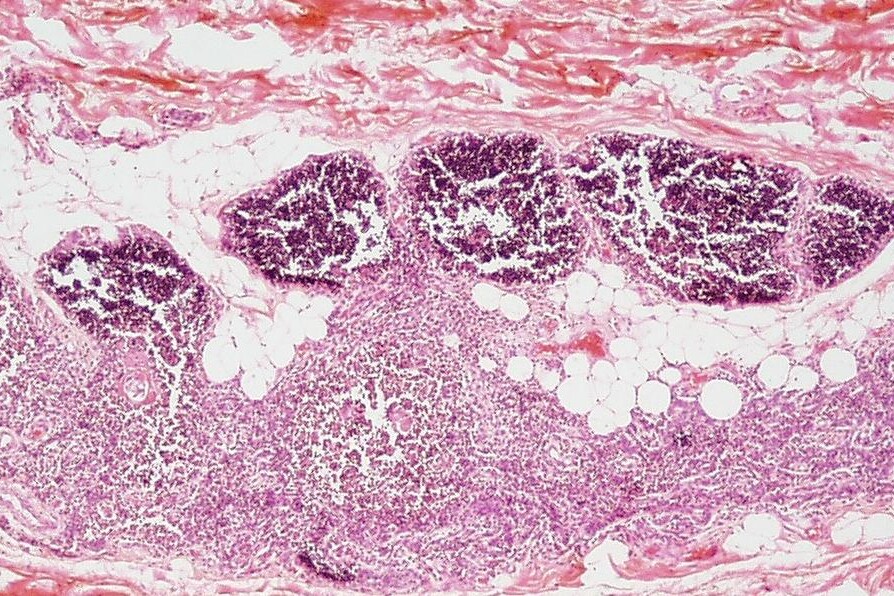

Zevní vrstva brzlíku se nazývá kůra a obsahuje velké množství lymfocytů. Uvnitř se nachází dřeň, která obsahuje vedle lymfocytů i další druhy buněk.

Brzlík je uložen v horní části hrudníku, kde leží těsně za hrudní kostí. U mladého dospělého člověka je jen několik centimetrů dlouhý a váží asi 15 g. Za tímto jednoduchým popisem se však skrývá skutečnost nejvýznamnější, a sice to, že tento dvoulaločnatý orgán, na rozdíl od všech ostatních, dosahuje největšího rozmachu v době puberty, kdy váží asi 45 g. Od té doby se zmenšuje a posléze zaniká a je nahrazen tukovou tkání.

Po pubertě se brzlík začíná zmenšovat, dochází k procesu zvanému involuce, takže u starších osob jej již nelze najít a na jeho původním místě je jen tuková a vazivová tkáň.